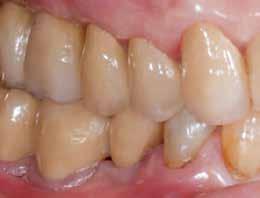

Preoperatív helyzet

Egy fiatal páciens jelentkezett nálunk, akinek eltörött a szabad véggel rendelkező hídja (1. ábra). A hiányzó, első premoláris fog esetén implantációs pótlást javasoltunk. A csontállomány értékeléséhez CBCT-vizsgálatot végeztünk, és az elemzéséhez NNT Viewert (NewTom) használtunk, és copaSKY 4×10 mm-es (bredent medical) implantátumot választottuk a fog pótlásához

1. ábra: Műtét előtti fogászati panorámafelvétel, amelyen a hiányzó felső állcsont jobb első premolárisát és a szabad véggel rendelkező hidat láthatjuk. — 2. ábra: Az implantátum méreteinek megtervezése CBCT-vel. 3. ábra: Bukkális lágyrészdefektus. — 4. ábra: A biológiai szélesség értékelése a vertikális lágyszövetvastagság alapján. 5. ábra: Palatinális „tekercslebeny” – Palatal roll flap. — 6. ábra: Bredent medical copaSKY 4x10 implantátumbeültetés. 7. ábra: Szubkresztális implantátumbeültetés a várható biológiai szélességnek megfelelően.

(2. ábra). A lágyszövetek értékelése Seibert szerinti I. osztályú csontdefektust állapított meg (3. ábra), ezért a beavatkozáskor palatinális „tekercslebenyt” preparáltunk (palatal roll flap), és implantációt végeztünk, hogy kompenzálni tudjuk a bukkális lágyszövet-behúzódást. Megmértük a vertikális lágyszövetvastagságot, és úgy terveztük, hogy a szubkresztális implantátum beültetése összhangban legyen a biológiai szélesség kialakulásával a transzgingivális gyógyulási periódus alatt (4. ábra)